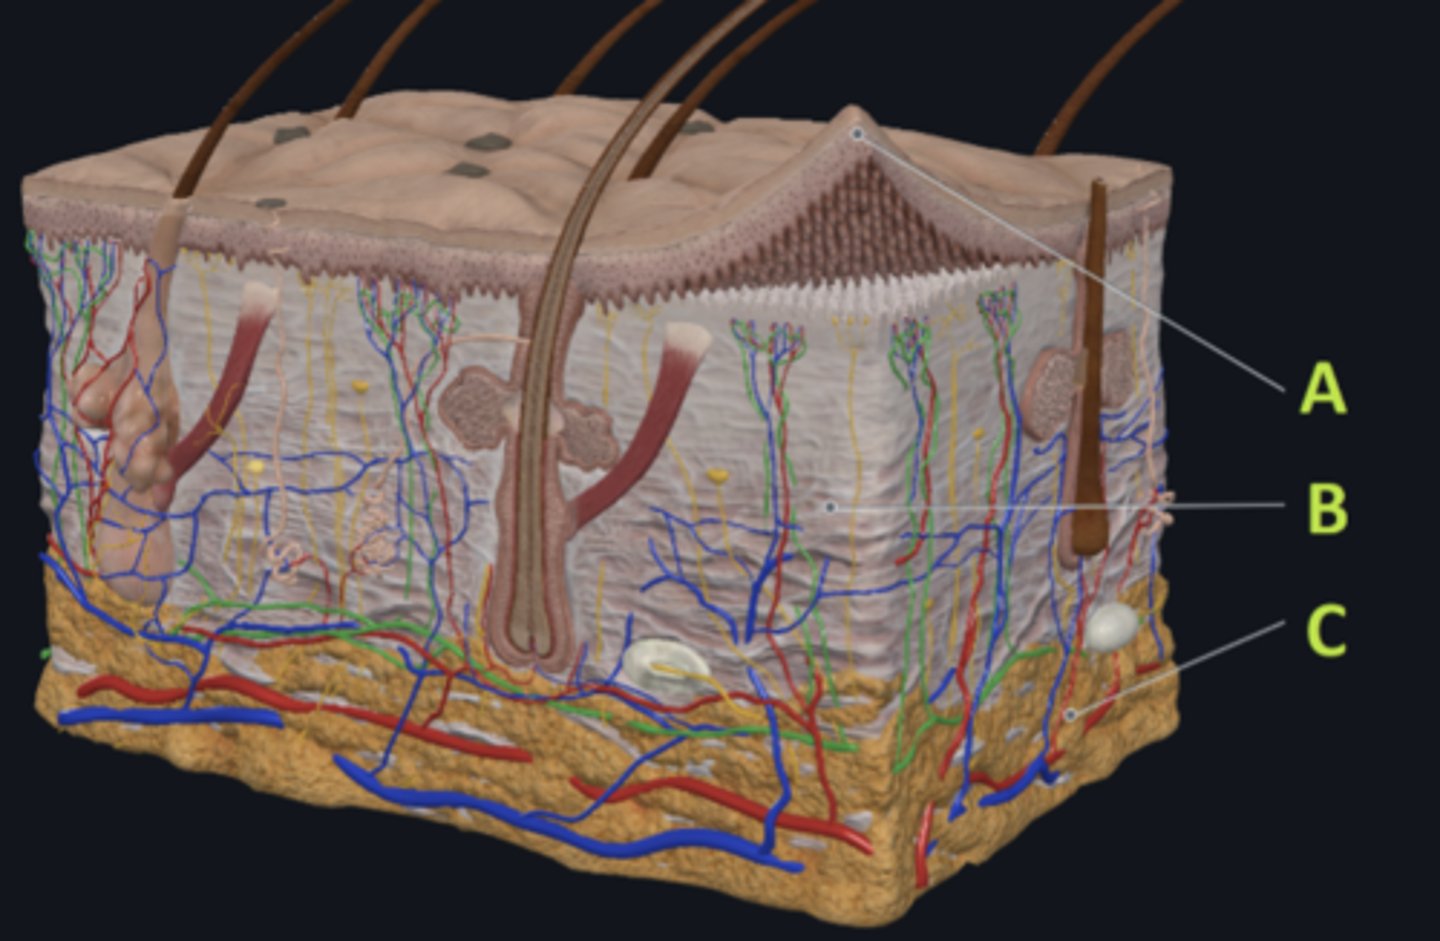

C - hypodermis

Answer the following questions based on the features indicated in the following image. Which letter indicates the administration site for subcutaneous injections?

A - epidermis

Answer the following questions based on the features indicated in the following image. Which letter indicates the administration site for topical creams and ointments?

B - Dermis

Answer the following questions based on the features indicated in the following image. Which letter indicates the administration site for the tuberculin skin test?

A - epidermis

Answer the following questions based on the features indicated in the following image. Which letter indicates a region of the skin with no nerves or blood vessels?

B - Dermis

Answer the following questions based on the features indicated in the following image. Which letter indicates the region where skin appendages (sweat glands, sebaceous glands, and hair follicles) have their roots?

Epithelial tissue

Answer the following questions based on the features indicated in the following image. Which of the four major tissue types is indicated by letter A?

Which letter indicates the administration site for insulin injections?

A

Which letter indicates the administration site for a lidocaine patch?

B

Which letter indicates the administration site for an allergy test?

B

Which letter indicates a region of the skin rich in dense, irregular connective tissue?

C

Which letter indicates the region most important for energy storage and thermal insulation?

Connective

Which of the four major tissue types is indicated by letter C?